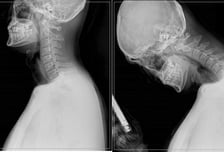

당신의 목 사진은 왼쪽? 오른쪽?…스마트폰 자주 봤더니

스마트폰 알람 소리에 눈을 뜨며 하루를 시작하는 현대인에게 스마트폰 없는 일상은 상상할 수 없다. 지난해 한국갤럽이 만 18세 성인을 대상으로 스마트폰 사용 여부를 조사한 결과, 2020년까지 90%대 초반이던 사용률은 2024년 98%까지 상승했다. 60대 이하의 사용률은 거의 100%에 이르고, 70대 이상 고령층에서도 90% 이상이 스마트폰을 사용하고 있다. 이에 따라 거북목, 일자목 증후군, 목 디스크 등 목 건강에도 '비상'이 걸렸다. ━ 장시간 고개 숙인 채 구부정한 자세...목과 척추 건강에 악영향━길을 걸을 때도, 지하철이나 버스에서도 스마트폰에 푹 빠져 있는 사람들을 흔히 볼 수 있다. SNS(소셜미디어), 게임, 쇼핑뿐 아니라 업무적인 소통까지 스마트폰은 일상을 점령하고 있다. 하지만 장시간 고개를 숙인 채 구부정한 자세를 유지하는 것은 필연적으로 목과 척추 건강에 악영향을 끼친다. 고개를 숙이면 머리가 떨어지지 않도록 붙잡는 목 근육의 수축력이 함께 작용하면서